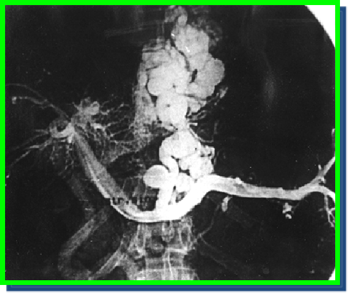

Смысл данного вмешательства заключается в разобщении портокавального перетока крови путем эмболизации левой желудочной и коротких вен желудка с помощью эмболизирующих материалов и металлической спирали Гиантурко, что позволяет снизить напряжение в варикозно расширенных венах желудка и пищевода и тем самым уменьшить риск кровотечения из варикозно расширенных вен пищевода и желудка (рис.14).

Рис. 14. Эндоваскулярнаяэмболизация левой желудочной вены и коротких вен желудка.

Эндоваскулярная эмболизация ВРВ желудка применяется с целью профилактики и лечения кровотечения из варикозно расширенных вен эзофагокардиальной зоны. Но она также эффективна при рецидивах кровотечений из вен желудка. Осуществить данную манипуляцию возможно только в клиниках, имеющих дорогостоящую рентгенангиографическую аппаратуру. Через 6 месяцев после первой процедуры необходимо повторять рентгенэндоваскулярную эмболизацию в связи с быстрой реканализацией тромбированных вен и высоким риском рецидива кровотечения. Данный метод выполним только у больных циррозом печени и проходимой воротной веной. Фатальным осложнением данной методики является продолженный тромбоз воротной вены и последующие неконтролируемые кровотечения из варикозно расширенных вен пищевода и желудка.